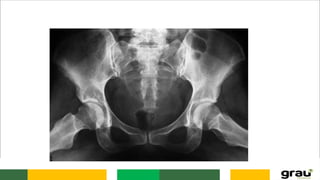

COLUNA VERTEBRAL (SACRO)

O sacro tem a forma de uma pirâmide quadrangular com a base voltada para cima e o ápice

para baixo. Articula-se superiormente com a 5ª Vértebra Lombar e inferiormente com o

Cóccix.

O sacro é a fusão de cinco vértebras e apresenta 4 faces: duas laterais, uma anterior e uma

posterior.